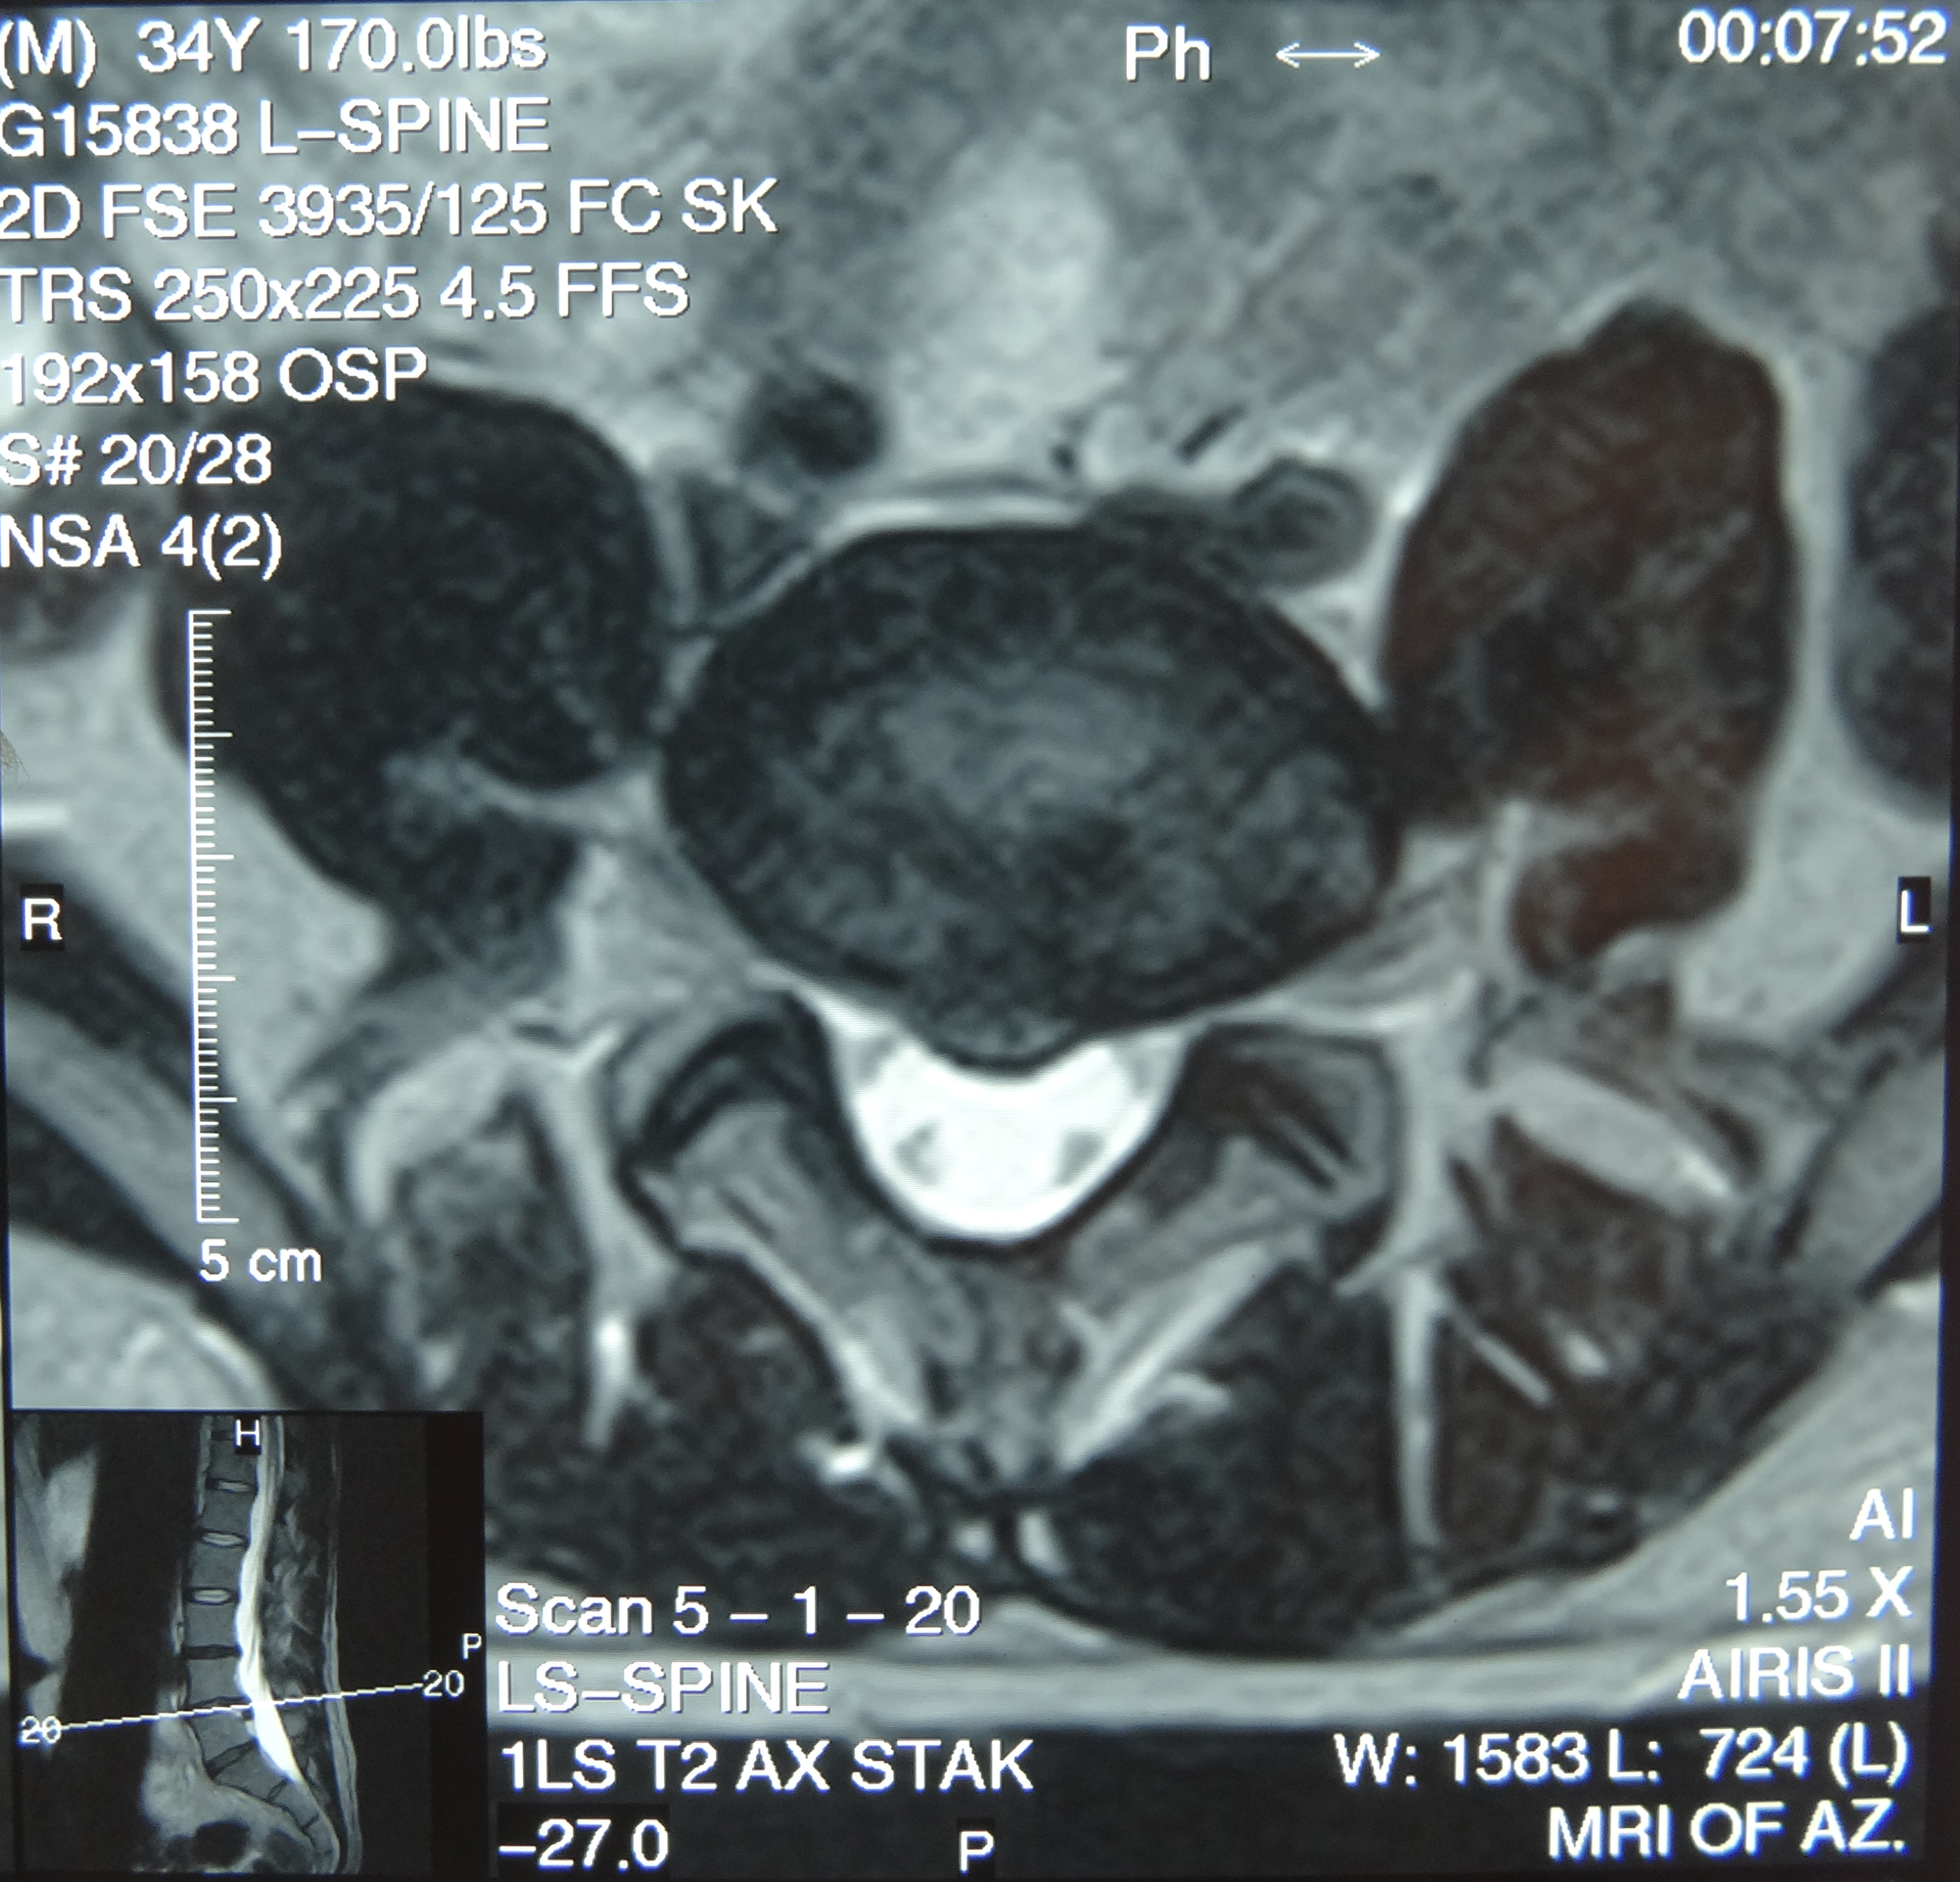

This patient presented with shoulder pain that interfered with work and exercise. The visible fluid-filled cysts on the “Before" MRIs are from chronically injured rotator cuff tendon roots.

The patient underwent treatments of a highly specialized fine-needling technique pioneered by Dr. Tallman.The follow-up MRI was done 2 months after his 6th treatment. He was released with a pain-free, full range of motion with unrestricted activities.